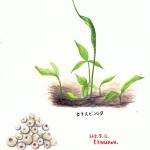

半夏

サトイモ科のカラスビシャクの塊茎。